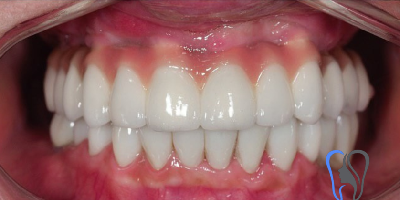

Case Study: Smile Makeover

- Procedure: Hollywood Smile (Zirconium Crowns)

- Patient: (Anonymous)

- Problem: Missing tooth, discolored, and damaged teeth.

- Time: 6 Days in Istanbul